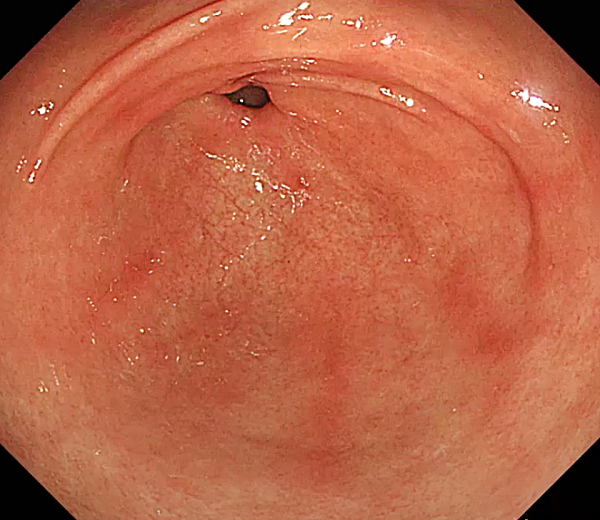

미란성 위염

- 위 점막에 얕은 상처(미란)가 생기는 위염입니다.

- 스트레스, 약물, 헬리코박터 파일로리균 감염 등으로 인해 발생합니다.

- 속 쓰림, 소화불량, 복통, 메스꺼움, 출혈 등의 증상이 나타날 수 있습니다.

- 원인에 따라 헬리코박터 파일로리 제균 치료, 위산 분비 억제제, 점막 보호제 등을 사용하여 치료합니다.

- 스트레스 관리 및 생활 습관 개선이 매우 중요합니다.